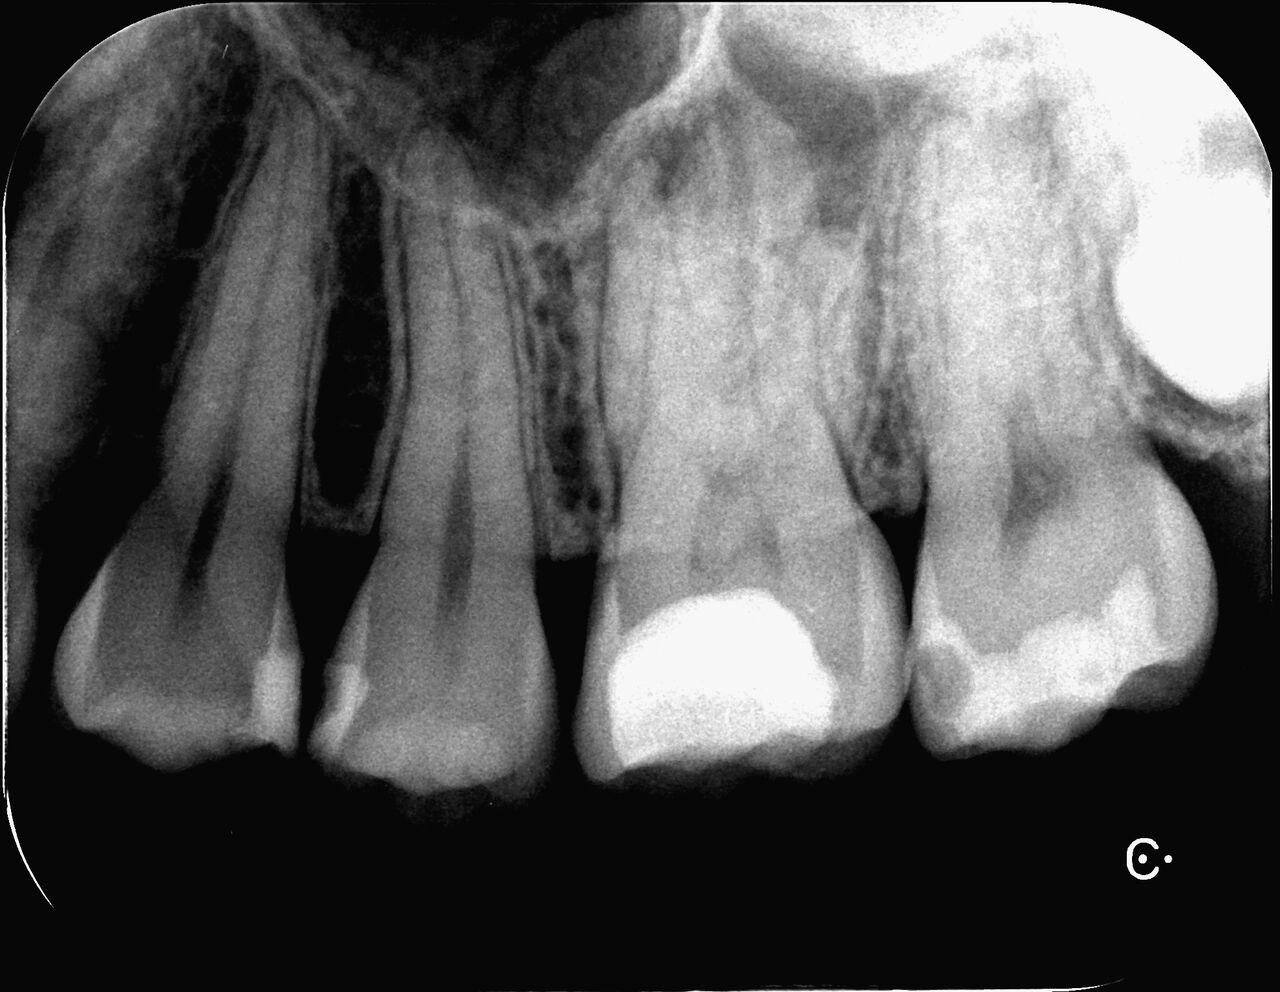

何回か根管治療をしました。

フィステルも消失し、痛みもなかったので治療は次のステップへ。

かなり歯質が残っていて、患者さんも削るのを嫌がったので、レジン治療へ。

ほとんどの歯質は残っており(特に機能咬頭)根管治療するための穴を塞いだくらいです。

井野先生ほど、小さく上手く開けれませんが、だいぶ歯質を残せました。